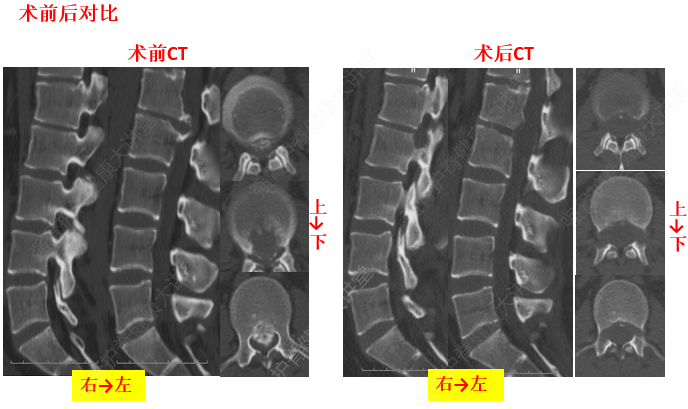

由于頸椎關(guān)節(jié)突間關(guān)節(jié)面近乎水平位,一旦椎間盤發(fā)生退變、椎間隙即變窄,關(guān)節(jié)囊及韌帶松弛,加上頸部活動時重力的影響,即可造成積累性損傷,加速頸椎退變和不穩(wěn),導(dǎo)致頸椎關(guān)節(jié)發(fā)生移位,使椎間孔變狹,椎管徑發(fā)生改變,壓迫神經(jīng)根或脊髓,產(chǎn)生臨床癥狀與體征。